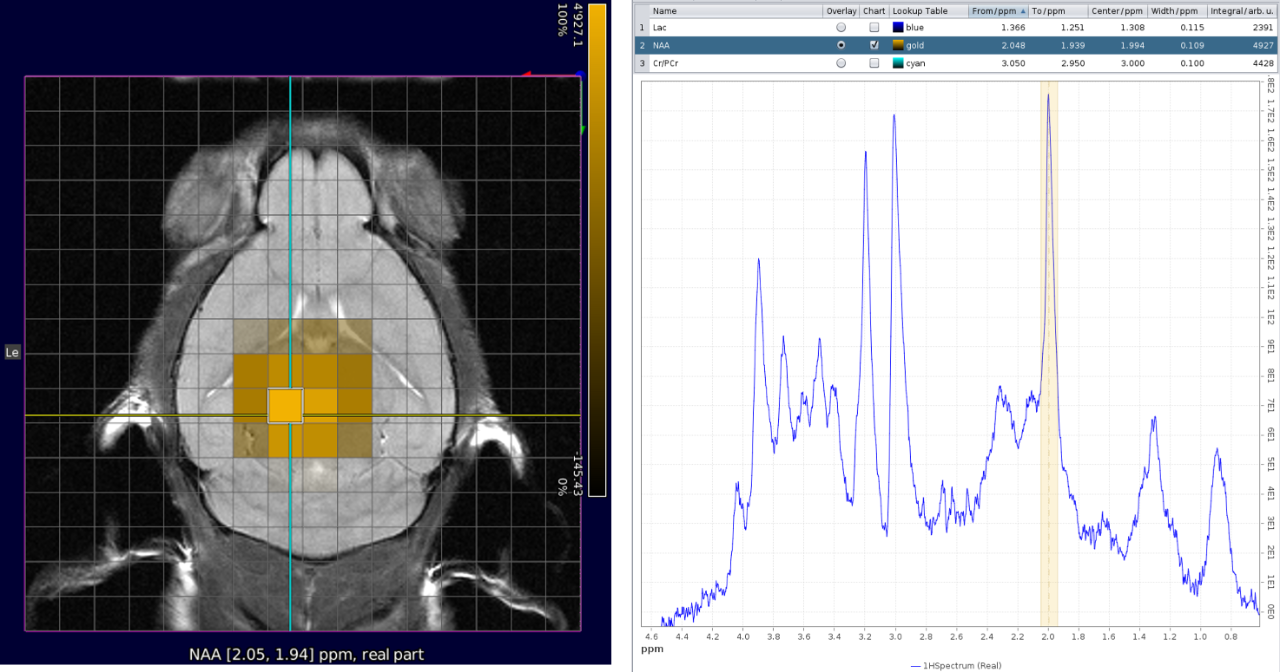

• Efficient visualization and processing of single voxel spectroscopy and chemical shift imaging spectroscopic data (e.g. CSI) with Spectroscopy Card

• Metabolic map creation and anatomical reference image overlaying

CSI with NAA frequency mapped